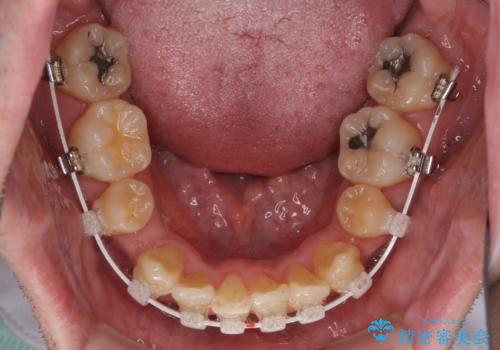

- 矯正装置

- 審美装置

治療開始直後は、あっという間に歯列が整い、すぐに終わるのではないかと思われましたが、治療の後半にブラックトライアングル解消のための処置を行ったため、当初予定していた2年半ほどの期間を要することとなりました。